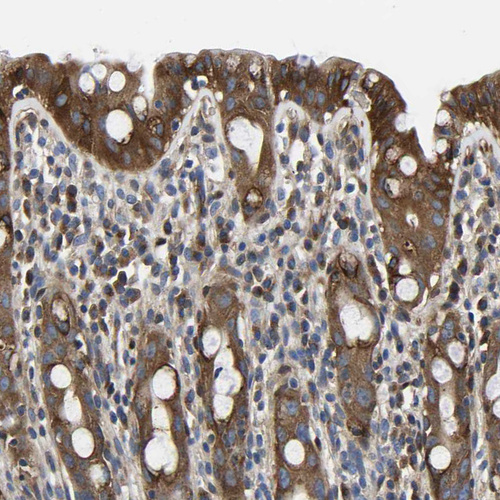

Immunohistochemical staining of human placenta shows strong cytoplasmic positivity in trophoblastic cells.